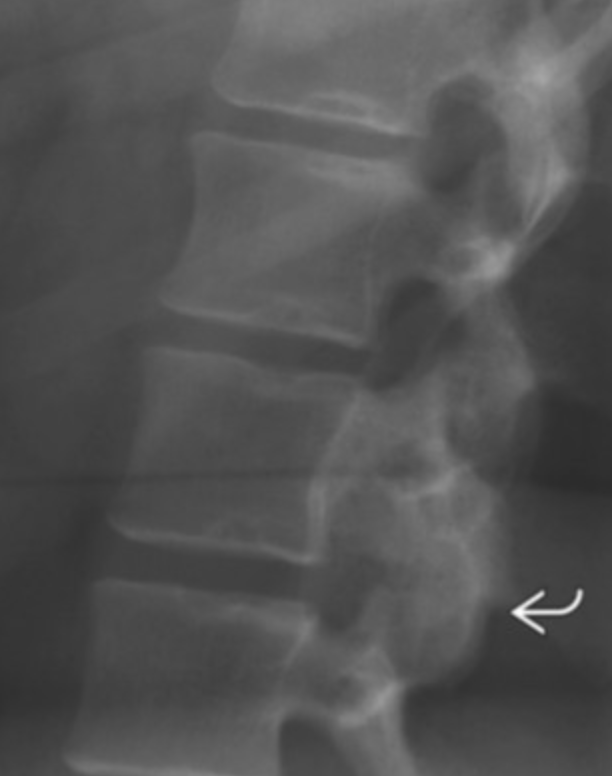

Chordoma

• Embryologic remnant of notochord

• Only occurs at midline

• Sacrococcygeal (50%)

• Clivus (30%)

• C2 vertebral body

• T2 bright & heterogenous

• Age 40-70

• Locally aggressive

• Mets possible in late stage